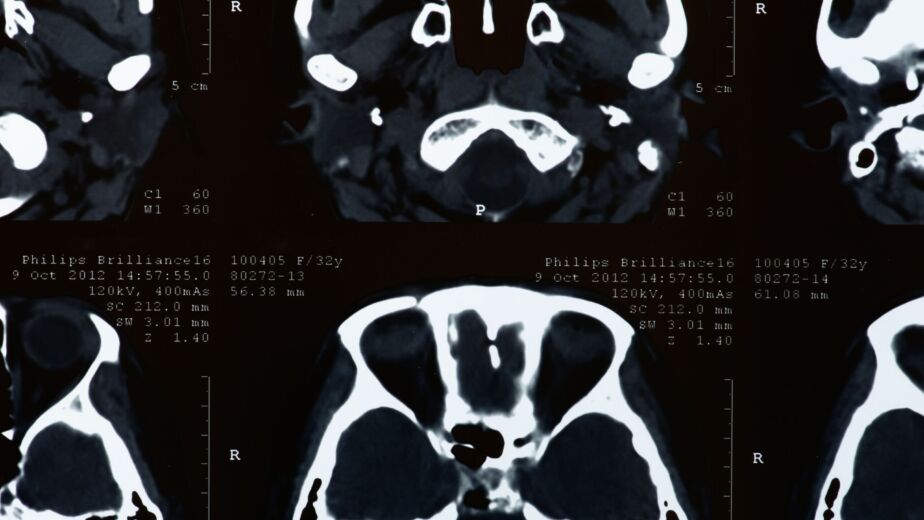

It was only five days after his first attendance — after Chris collapsed at home and was brought in by ambulance — that an urgent MRI was finally performed. The scan confirmed a massive central disc prolapse at L4/5 compressing the cauda equina nerve roots. Emergency decompression surgery was carried out, but the cumulative delay caused by repeated medical negligence had already resulted in irreversible nerve root damage.